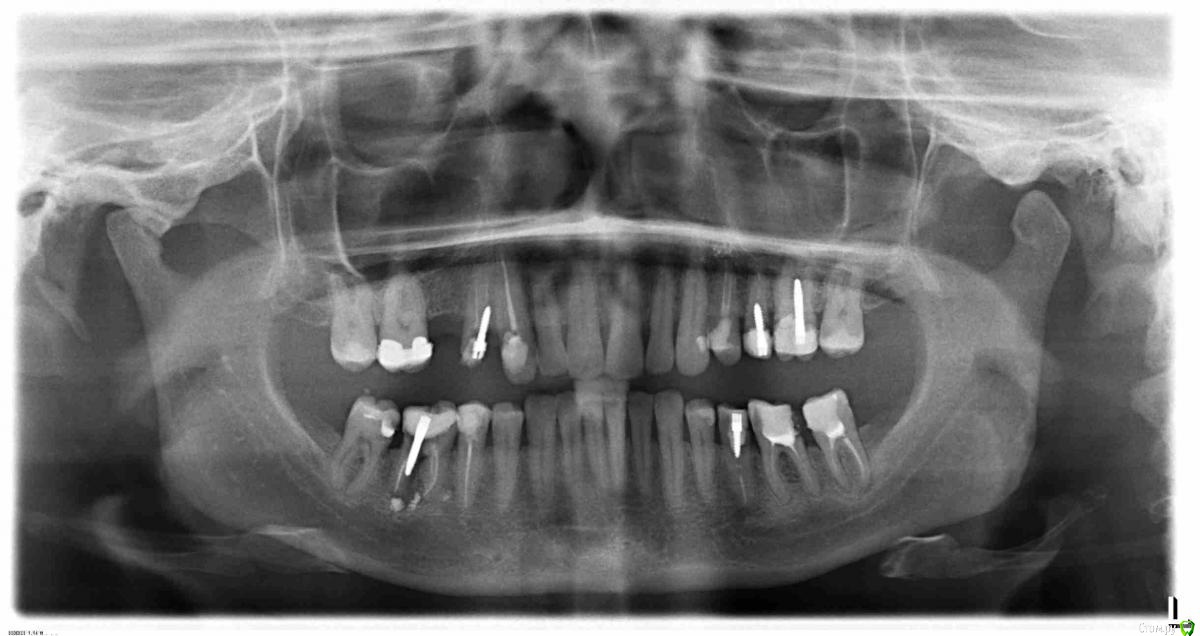

alexloco Опубликовано 15 декабря, 2014 Поделиться Опубликовано 15 декабря, 2014 (изменено) Добрый день, уважаемые доктора.У жены развалился 13 и 14, сделали снимок, пошли к докторам.И тут нас напугали: на удаление 14 и 46, а также под вопросом 25, 26 и 35. Решил посоветоваться с Вами, действительно все так плохо, или можно с этим жить?? Зубы вроде не болят. Штифты ставились лет 7 назад.Есть ли где нибудь парадантоз, или надо делать точечные снимки?Может где поставить коронки, или ввернуть имплантант? Изменено 15 декабря, 2014 пользователем alexloco Ссылка на комментарий

red_butler Опубликовано 15 декабря, 2014 Поделиться Опубликовано 15 декабря, 2014 1.4 и 4.6 точноудалять, еще несколько зубов по вопросом Ссылка на комментарий

Korel Опубликовано 15 декабря, 2014 Поделиться Опубликовано 15 декабря, 2014 Навскидку набросал проблемы видимые на ОРТО http://s009.radikal.ru/i310/1412/95/e7d0300c7d20.jpg Всё зависит от того что Вы хотите делать? 1. Оставить всё так как есть - следствие: различные вяло или остро протекающие осложнения.2. Планируете сделать рот , что называется "под ключ" - как уже писал выше коллега - удалять 14 и 46, в 46 уже есть резорбция(убыль) костной ткани. Чем дольше этот зуб остаётся тем больше будет прогрессировать резорбция. + полная санация полости рта, т.е. разбор зелёных стрелок и кружков. А вот затем можно думать о коронках и имплантах) 3 Ссылка на комментарий